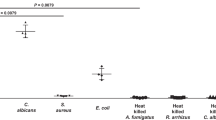

In vitro uptake of 68Ga-PVD-PAO1 by microbial cultures

Uptake of 68Ga-PVD-PAO1 by P. aeruginosa was highly dependent on the bacterial culture conditions. Iron-deficient but not iron-sufficient cultures displayed high uptake that could be blocked with an excess (10 µM) of cold iron PVD-PAO1 and partly with NaN3, indicating a specific and energy-dependent uptake mechanism (Fig. 2A). Uptake was observed up to 90 min after incubation without saturation, again sensitive to blocking with Fe-PVD-PAO1 (Fig. 2B). Uptake study of different siderophores not produced by P. aeruginosa radiolabelled with Ga-68 in iron-deficient P. aeruginosa cultures showed negligible uptake of these compounds compared to 68Ga-PVD-PAO1 (Fig. 3A). Figure 3B summarizes the uptake of 68Ga-PVD-PAO1 in different microorganisms. Under iron-deficient conditions 68Ga-PVD-PAO1 showed much higher uptake by P. aeruginosa compared to other tested microbial cultures in which minor or no uptake was observed, indicating high specificity of 68Ga-PVD-PAO1 for P. aeruginosa.

(A) In vitro uptake of 68Ga-PVD-PAO1 in P. aeruginosa after 45 min of incubation under varying conditions (2 mM sodium azide and excess of Fe-PVD-PAO1) in iron-deficient and iron-sufficient conditions. (B) In vitro uptake of 68Ga-PVD-PAO1 in P. aeruginosa over time under iron-deficient conditions and in the presence of excess of Fe-PVD-PAO1.

(A) In vitro uptake of different Ga-68 labelled siderophores in P. aeruginosa after 45 min of incubation under iron-deficient conditions. (B) In vitro uptake of 68Ga-PVD-PAO1 in various microbial cultures (Pa1 = Pseudomonas aeruginosa ATCC 15692, Pa2 = Pseudomonas aeruginosa 1019, Bm = Burkholderia multivorans 1926, Bc = Burkholderia cenocepacia 2029, Sa = Staphylococcus aureus 230, Ca = Candida albicans 1265, Pg = Pseudomonas grimontii 754, Pm = Pseudomonas monteilii 2260, Sag = Streptococcus agalactiae 487, Kp = Klebsiella pneumoniae 2102, Ec = Escherichia coli 2463, Sm = Stenotrophomonas maltophilia 303, Ye = Yersinia enterocolitica 2871, Lm = Listeria monocytogenes, Ab = Acinetobacter baumannii 2377) after 45 min of incubation under iron-deficient conditions.

68Ga-PVD-PAO1 showed hydrophilic properties, low protein binding and high stability in human serum. In vitro assays displayed rapid and high uptake increasing over time (up to 90 min) by P. aeruginosa under iron-deficient conditions, which could be blocked with excess of Fe-PVD-PAO1 or sodium azide. The lower extent of uptake reduction under the addition of sodium azide confirmed the phenomenon that especially in iron-deficient conditions not only transporters are up-regulated, but also siderophore binding proteins, leading to increased cell surface binding of Fe/68Ga-siderophores15.

It is known that numerous microorganisms possess specific uptake systems not only for native siderophores, but also for siderophores synthesized exclusively by other pathogens, so called “xenosiderophores”35. Therefore, in vitro uptake studies of selected 68Ga-siderophores in P. aeruginosa and 68Ga-PVD-PAO1 in different microorganisms were performed. None of tested 68Ga-siderophores was significantly taken up by P. aeruginosa and the uptake of 68Ga-PVD-PAO1 was highly specific for P. aeruginosa cultures. In animals, 68Ga-PVD-PAO1 showed excellent pharmacokinetic properties with rapid renal elimination from non target tissue, selective accumulation in infected tissues and great sensitivity enabling the detection of only five viable cells of P. aeruginosa. Moreover, 68Ga-PVD-PAO1 displayed better specificity and pharmacokinetic properties than other, clinically used radiopharmaceuticals.